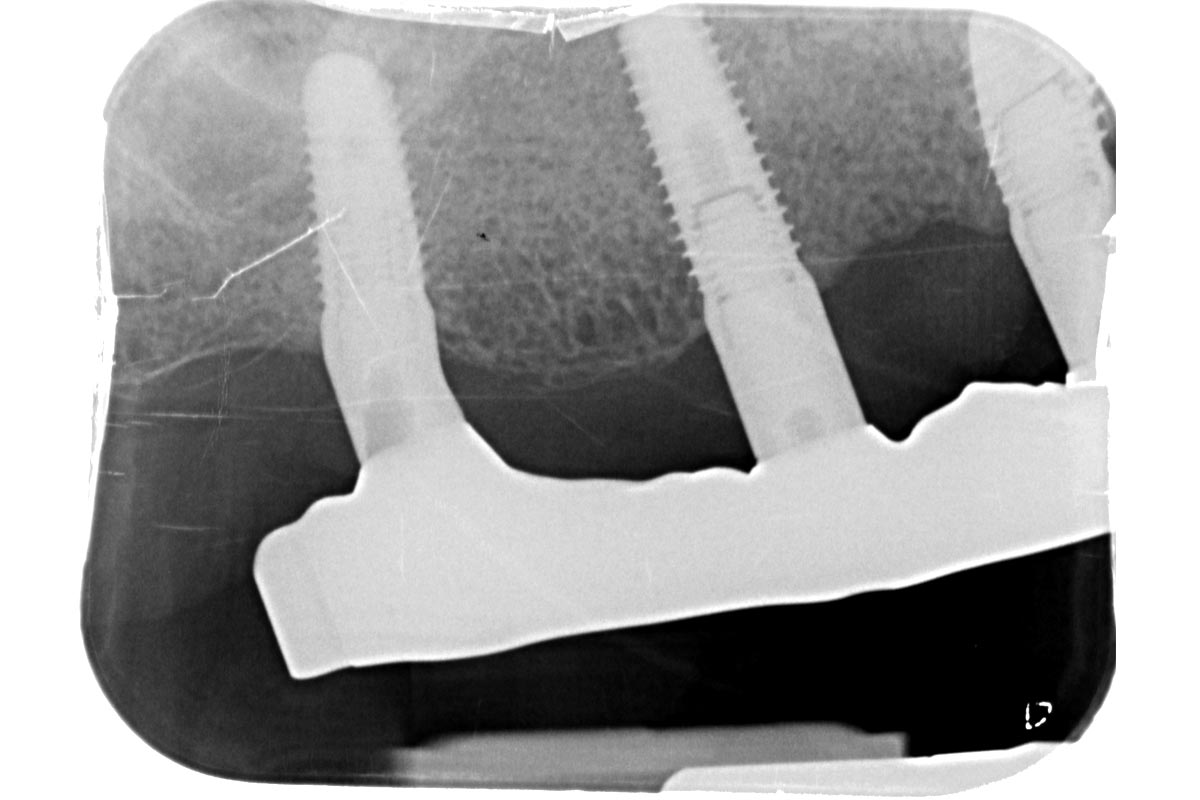

Initial x-ray showing bone loss around implants placed 5 years ago in another dental clinic